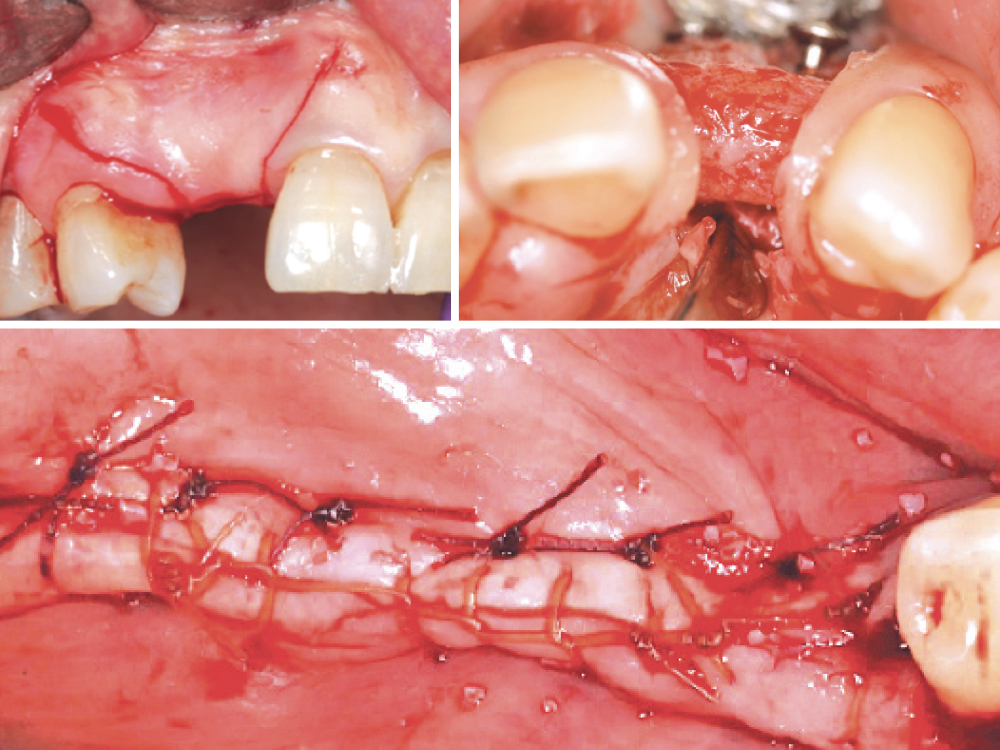

When this wound breakdown occurs, an increased morbidity for dental implant surgery and bone grafting may result because of bacterial contamination (Figs. 1a, 1b). In this article, various techniques and protocols will be discussed to prevent ILO and manage this complication.

Incision line opening: (a) implants, (b) guided bone regeneration procedures.

Figures 1a, 1b: Incision line opening: (a) implants, (b) guided bone regeneration procedures.